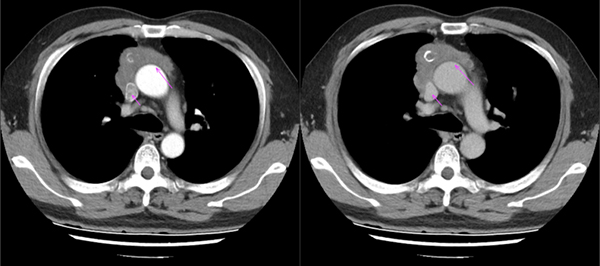

图:老康的CT片,肿物位于右侧纵隔,侵犯上腔静脉(短箭头)和主动脉(长箭头),腔静脉已出现受压性扩张

经过详细检查评估,老康的肿瘤已经长到和一个香瓜一般大小,瘤体已经充满了老康的整个纵隔。心脏、膈神经受侵,右肺门区域受侵,肿瘤已包裹上腔静脉,主动脉、气管等重要结构已严重移位,手术难度极大,风险极高。